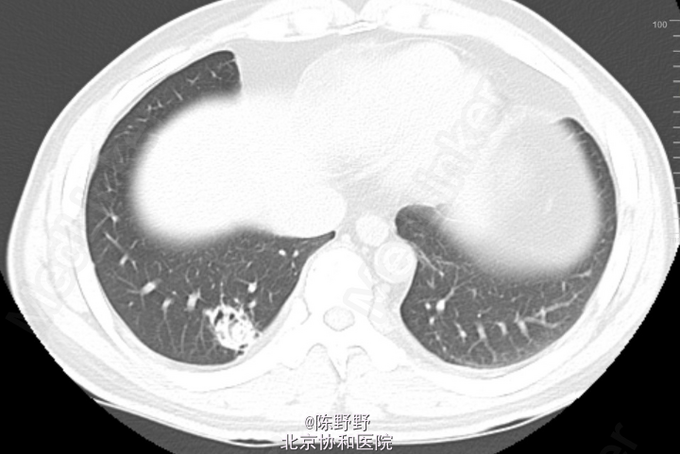

咳嗽、痰中带血丝半年

无特殊 CT提示右下肺空洞内见团状物

术前诊断考虑曲霉菌球,恶性病变不能除外 行VATS右肺下叶切除,术中切开见囊性病变内灰黑色团状病变,考虑曲霉菌球,最终病理明确诊断